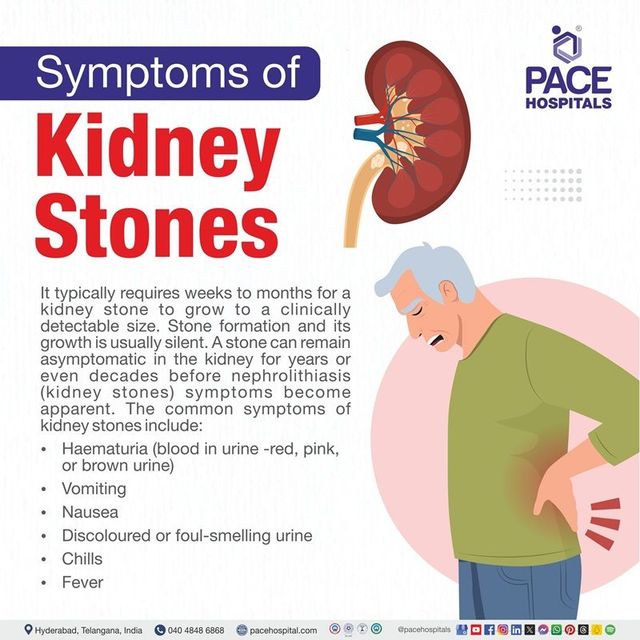

How to know if you have kidney stones discount, Symptoms of Kidney Stones discount

Signs You May Have Kidney Stones Blog Loyola Medicine- how to know if you have kidney stones